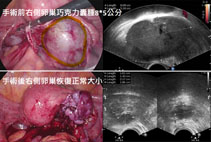

The Impact of Surgery on Ovarian Function

When

medical treatment fails, surgery is often recommended to remove ovarian

endometriomas and alleviate symptoms. While surgery can improve quality of

life, it may also compromise ovarian function, and endometriosis has a high

recurrence rate, sometimes necessitating repeat surgeries. Medication after

surgery can help reduce recurrence risks.

After

surgery, ovarian function may decline, especially if multiple surgeries are

performed. This can lead to a lower egg yield in future fertility treatments.

For young women who have not yet had children or those with already diminished

ovarian reserve, egg freezing before surgery is strongly recommended to

preserve fertility.